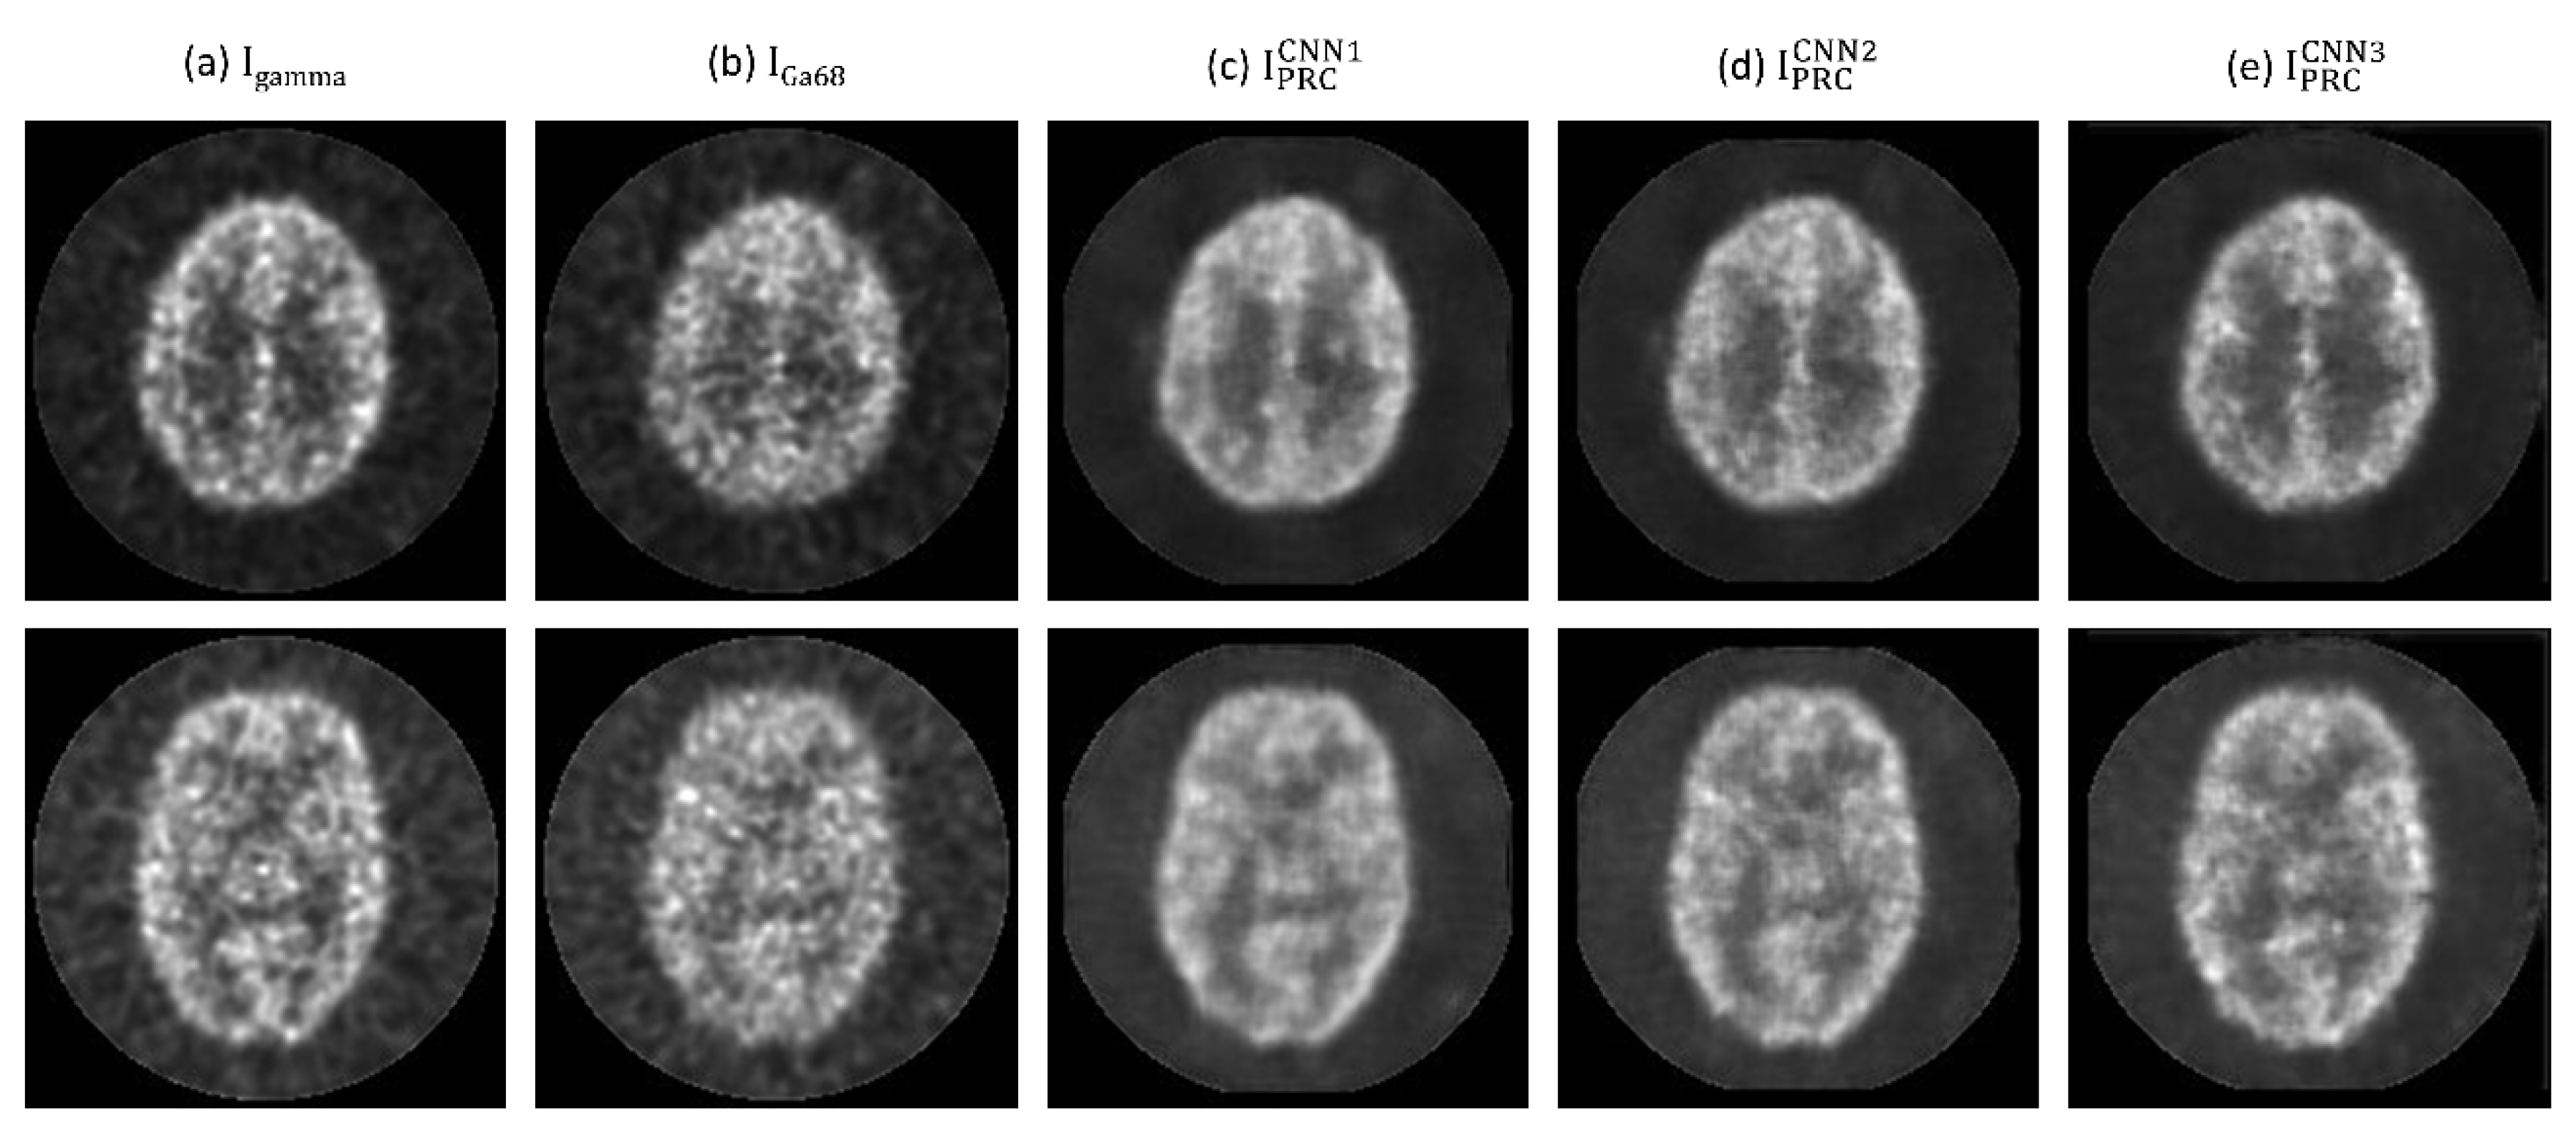

3. Results